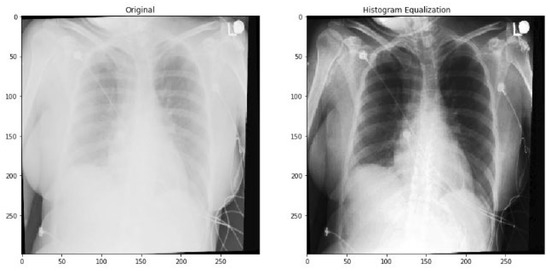

2.1. Data Pre-Processing